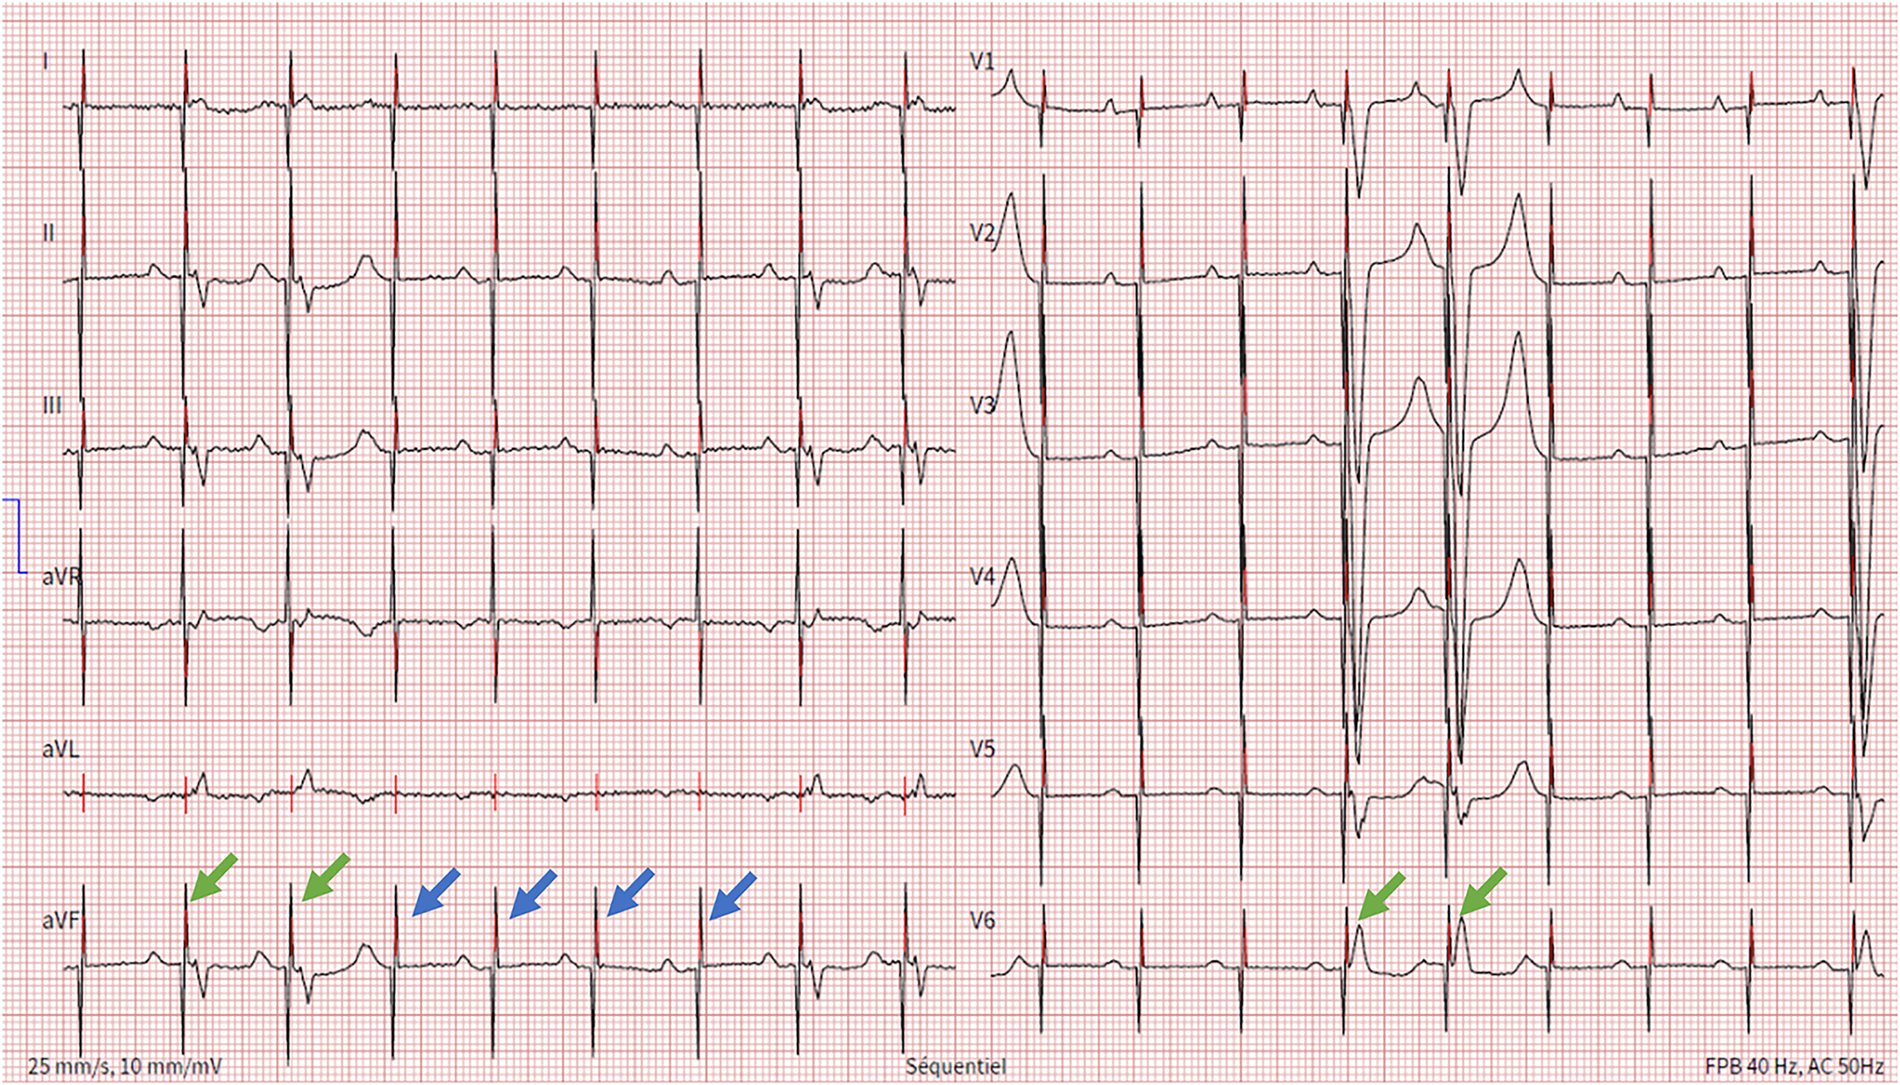

Figure 1

Electrocardiogram showing spontaneous P wave activity followed by unipolar ventricular stimulation spikes that most of the times are ineffective (blue arrows) and rarely result in ventricular capture (green arrows).